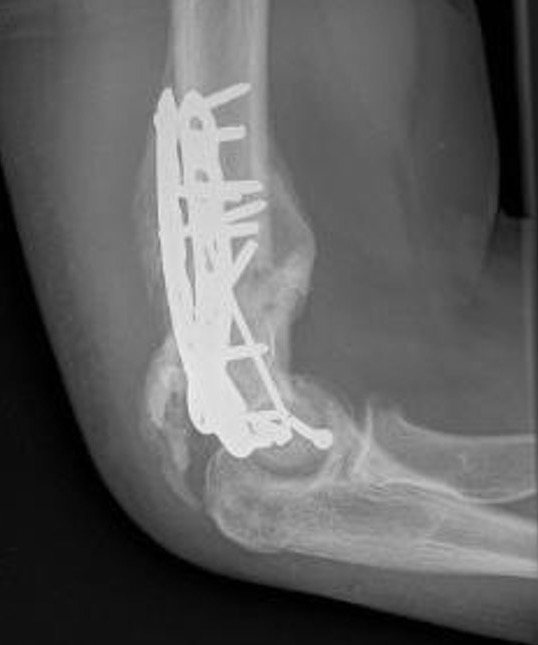

Fixation techniques

Options

Precontoured anatomical plates

Parallel plates v perpendicular plates

Locking v non locking screws

Parallel v perpendicular plates

Parallel plates - medial plate on medial column and lateral plate on lateral column

Perpendicular plates - plates at 90 degrees, with lateral plate posterior

- cadaveric model

- biomechanical superiority of parallel plates versus perpendicular plates

- systematic review of 83 studies and 2362 patients

- parallel plating lower incidence of revision for fixation failure (1% v 6%)

- perpendicular plating reduced overall complication (45% v 54%)

- these complications included lower incidence neuropathy, wound dehiscence, and implant prominence

Results ORIF

- 30 patients at a mean follow up of 19 years

- 87% good or excellent result

- mean flexion / extension arc 106 degrees

- 80% had evidence of OA on xrays

- mostly mild or moderate and not clinically significant